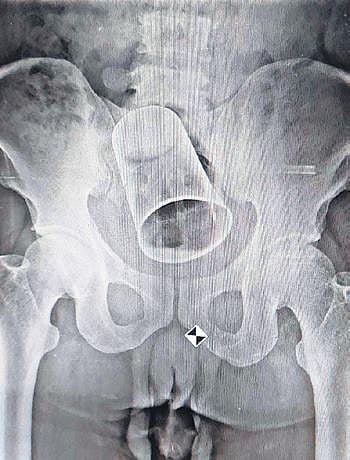

He was rushed to MKCG where an X-ray of his abdomen was conducted. The scan showed that the tumbler was stuck in Rout’s intestine. The doctors tried to remove the tumbler through Rout’s anus but failed. “As surgery was the only option, I advised my team to remain prepared,” said Prof Panda.